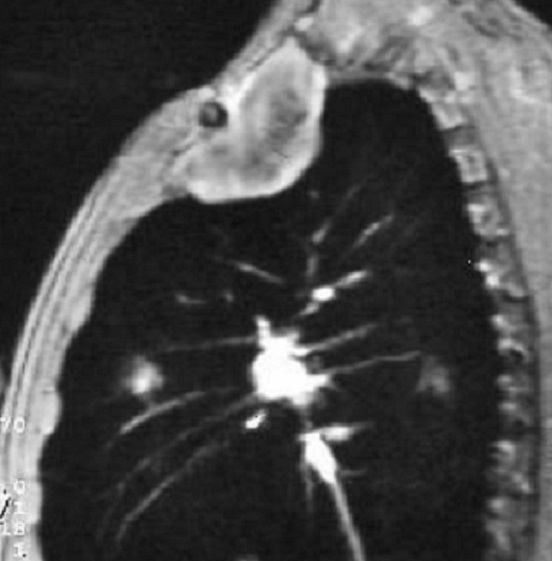

Image radiologique IRM : Aspect lesionnelle IRM est hypo à

isosignal ; rehaussement heterogene sur T1 avec Gd injection

intraveineuse ; hypersigal heterogene sur T2 avec aspect

de hyposignal en strie de cheveux du lesion